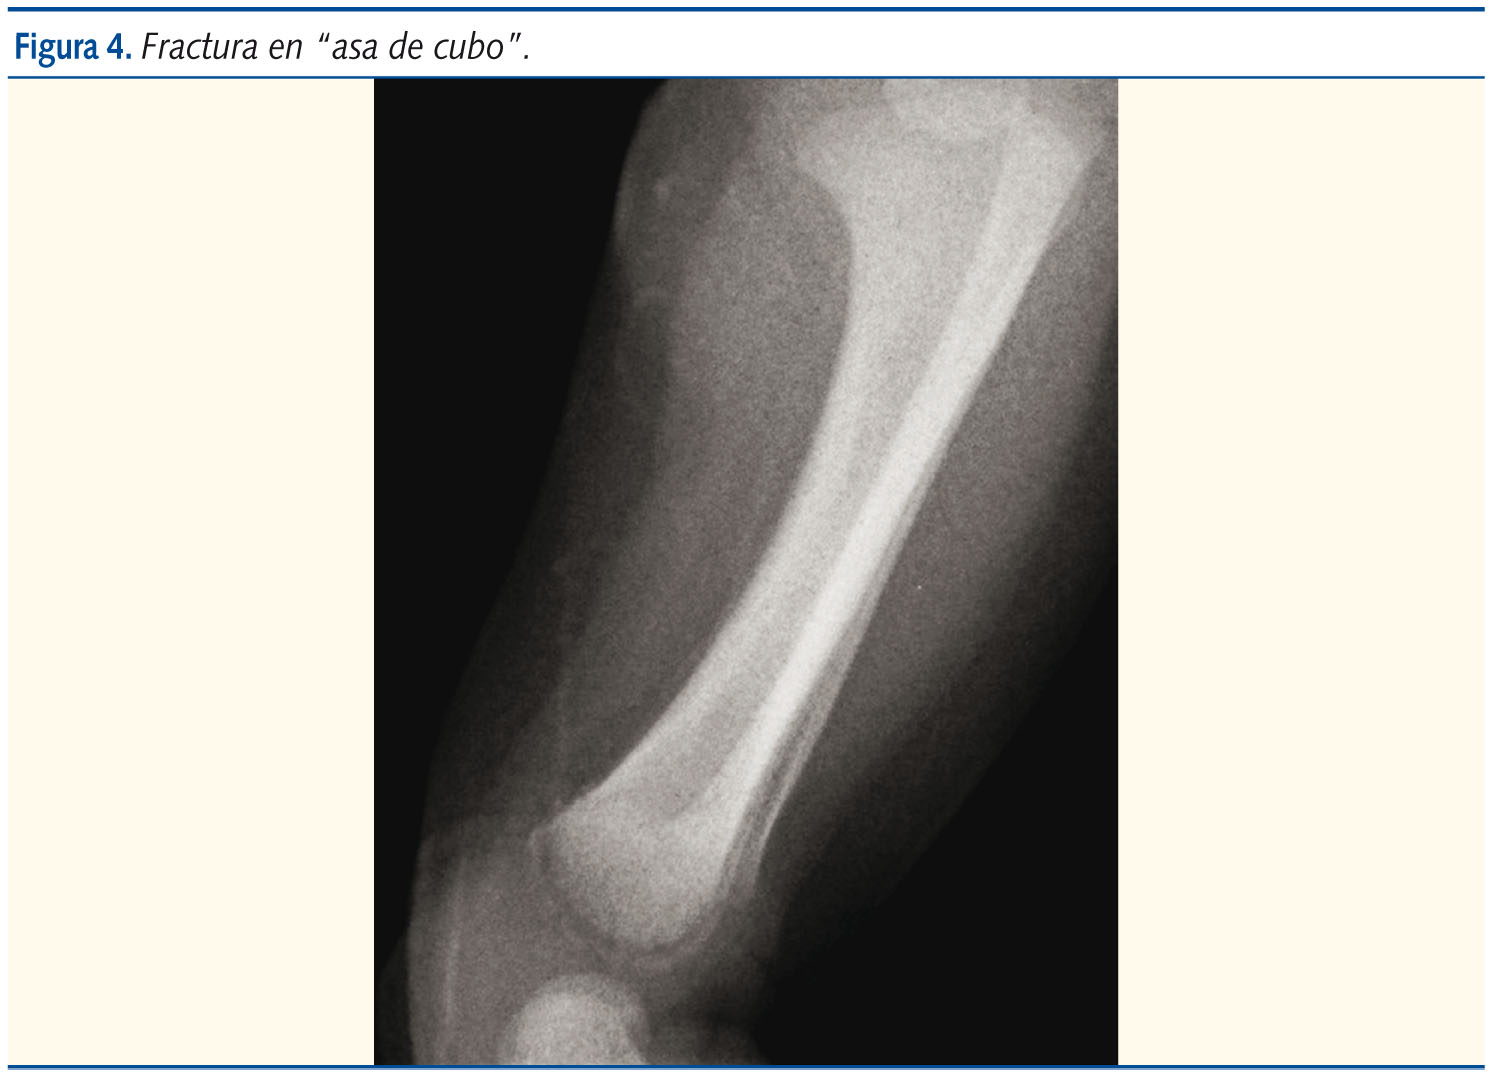

Claves diferenciales con respecto al adulto: elasticidad, capacidad de remodelación y presencia del cartílago de crecimiento.

Fractura del niño que empieza a caminar. El apoyo inestable provoca, en algún momento, una torsión del miembro inferior sobre sí mismo, que se traduce en una fractura espiroidea, casi siempre de tibia. Una fractura Toddler previa a la marcha es altamente sugestiva de síndrome de maltrato infantil.

No es patología de hospital de referencia: el tratamiento de las fracturas no tiene especial complejidad, y las secuelas radiológicas llegan a cualquier consulta externa o centro de Atención Primaria.